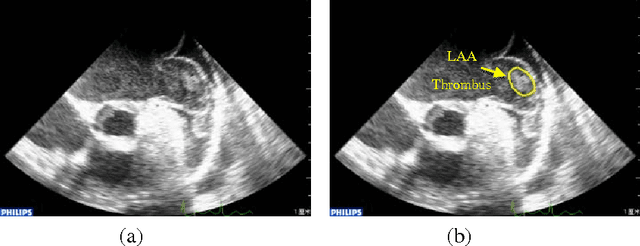

Abstract:Transesophageal echocardiography (TEE) is widely used to detect left atrium (LA)/left atrial appendage (LAA) thrombi. In this paper, the local binary pattern variance (LBPV) features are extracted from region of interest (ROI). And the dynamic features are formed by using the information of its neighbor frames in the sequence. The sequence is viewed as a bag, and the images in the sequence are considered as the instances. Multiple-instance learning (MIL) method is employed to solve the LAA thrombi detection. The experimental results show that the proposed method can achieve better performance than that by using other methods.